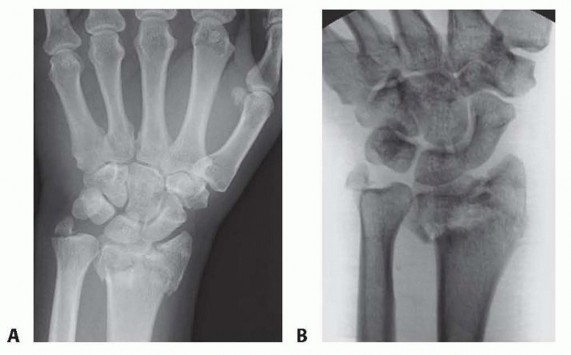

TECH FIG 1 • Radiographs show an anteroposterior (AP) projection of the wrist injury before (A) and after